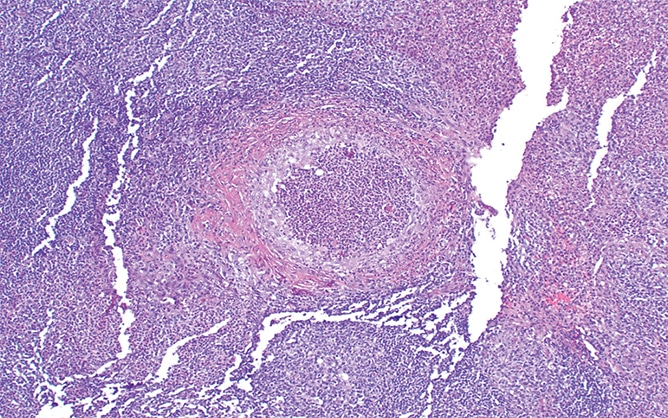

The resection specimen contained suppurative granulomatous appendicitis and active chronic enterocolitis (Figs. 1–3). Granulomatous inflammation was also noted in the endoscopic biopsies of the right colon (Fig. 4), explained Dr. Zenali, assistant professor of pathology, Department of Pathology and Laboratory Medicine, UConn Health.

Yersiniosis often involves the terminal ileum/ileocecal region and mesenteric lymph nodes; it may also affect the appendix. Suppurative and granulomatous patterns are common in Yersinia enterocolitica and in particular in Yersinia pseudotuberculosis, Dr. Zenali said. “Patients can have concurrent mesenteric lymphadenitis. The organism accesses the bowel wall through the microfold [M] cells of the Peyer’s patches, so the inflammatory reaction often initiates from the terminal ileum and ileocecal valve and can further spread to the right colon.”